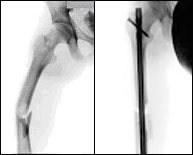

We refer in this section to the middle portion of the femur also called mid-shaft fractures. Fractures in this location are frequently associated with high-energy trauma such as traffic accidents or falls from great heights as well as high speed sports. Manu times femoral fractures are associated with fractures in other locations called poly-trauma injuries. There have also been reported stress fractures in competitive athletes after repetitive overuse but these are very rare situations. The treatment is always surgical stabilization. An intramedullary nail is placed through a minor incision to restore leg strength and start walking as soon as possible.